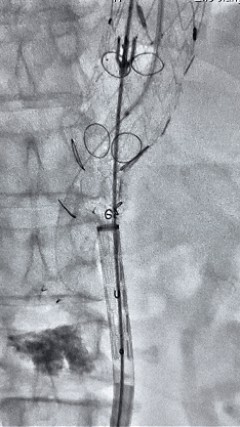

8. 从右侧股动脉入路送入腹主支架AB-24-12-110-S,近端沉叠胸腹自动脉支架远端,调整好支架地位后开释。

9. 经左股动脉送入导丝导管,超选进腹自动脉支架短腿内,后沿导丝送入髂支,同理,右侧沿导丝送入髂支并开释,使用俄罗斯贵宾会集团适应性球囊后扩各支架衔接处及支架近远端,最后通过预留导管向瘤腔注入人纤维蛋白粘合剂数支,造影显示分支畅达。

术后评价

G-Branch在本例手术中展示出对扭误会剖结构的杰出适应性,针对该患者严沉扭曲的瘤颈,支架系统的优异柔顺性使其可能顺利通过复杂蹊径,实现内脏分支血管的沉建。

其怪异的双内嵌、双表翻混合多分支设计两全了操作效能与结构靠得住性,预置导丝系统简化了肠系膜上动脉(SMA)撼构腔干动脉(CA)的超选流程,显著提高手术效能。